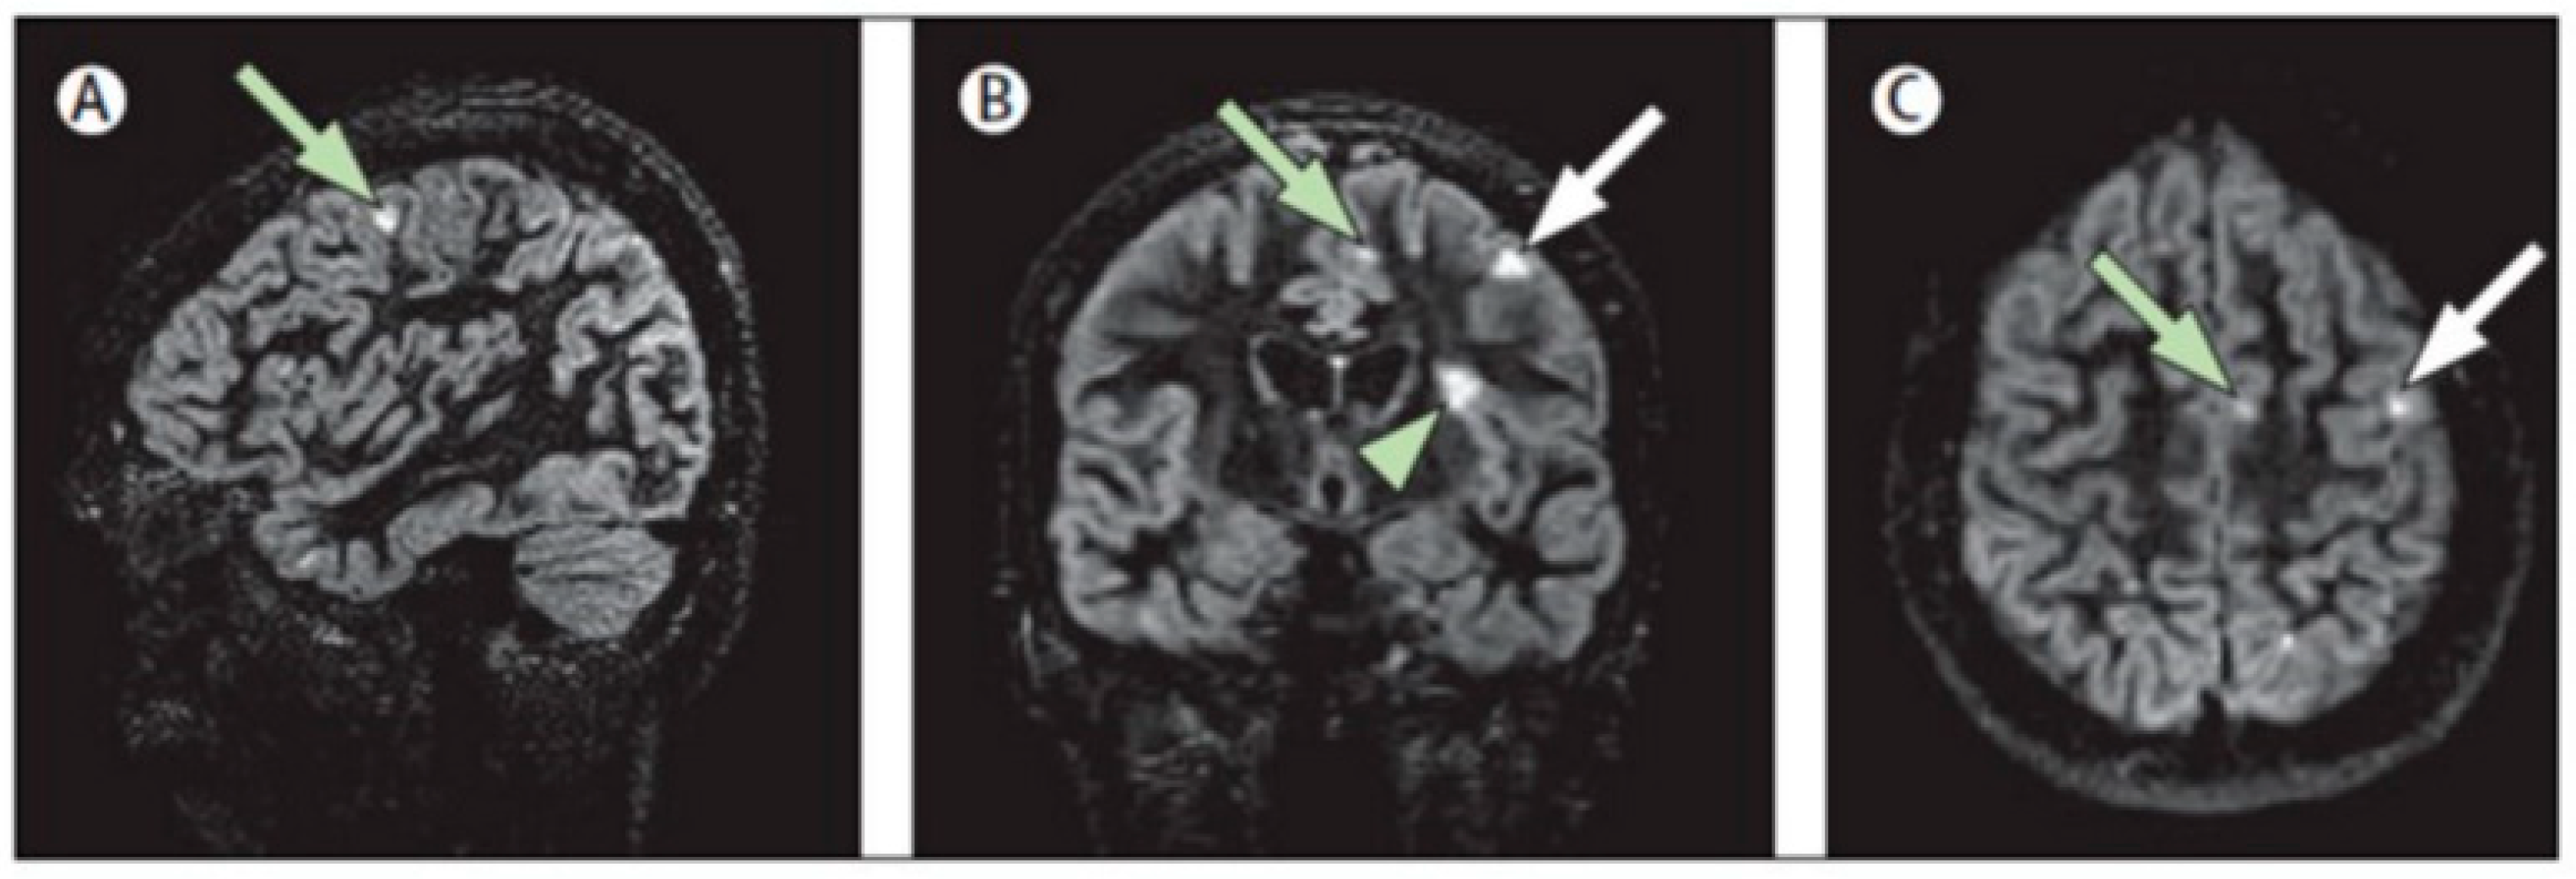

- Cocozza, S.; Cosottini, M.; Signori, A.; Fleysher, L.; El Mendili, M.M.; Lublin, F.; Inglese, M.; Roccatagliata, L. A clinically feasible 7-Tesla protocol for the identification of cortical lesions in Multiple Sclerosis. Eur. Radiol. 2020, 30, 4586–4594. [Google Scholar] [CrossRef]